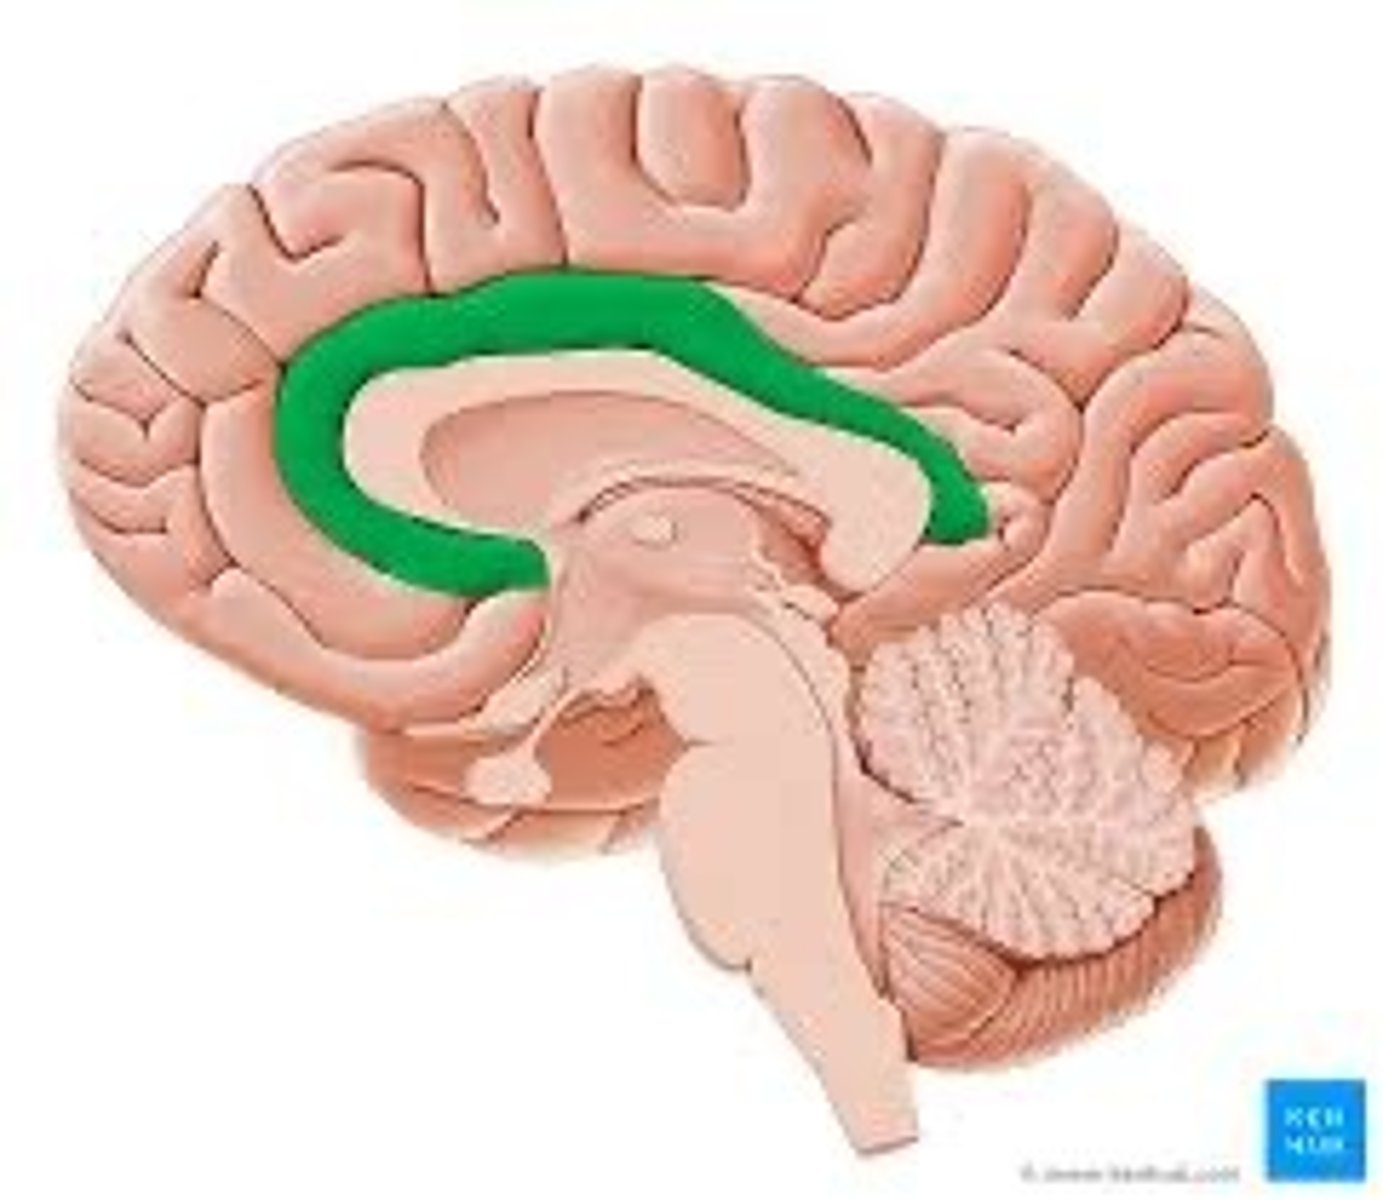

Corpus callosum

structure, first sombrero

Cingulate gyrus

ridge, bigger sombrero